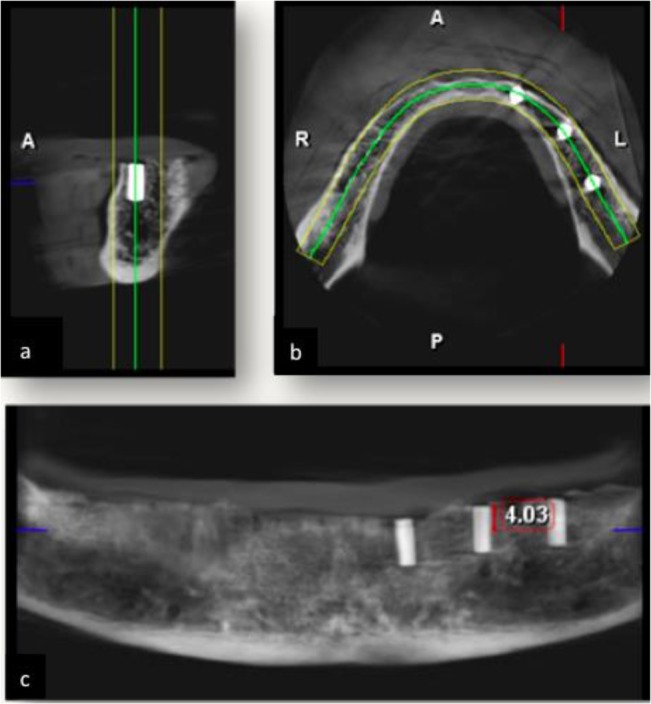

The axial plane, which was perpendicular to the middle rod and located 4mm from its superior surface was selected as the reference axial plane (Fig. 3) and was saved as the two-dimensional form (Fig. 4).

Fig. 3:

(a) Sagittal, (b) axial and (c) panoramic images.